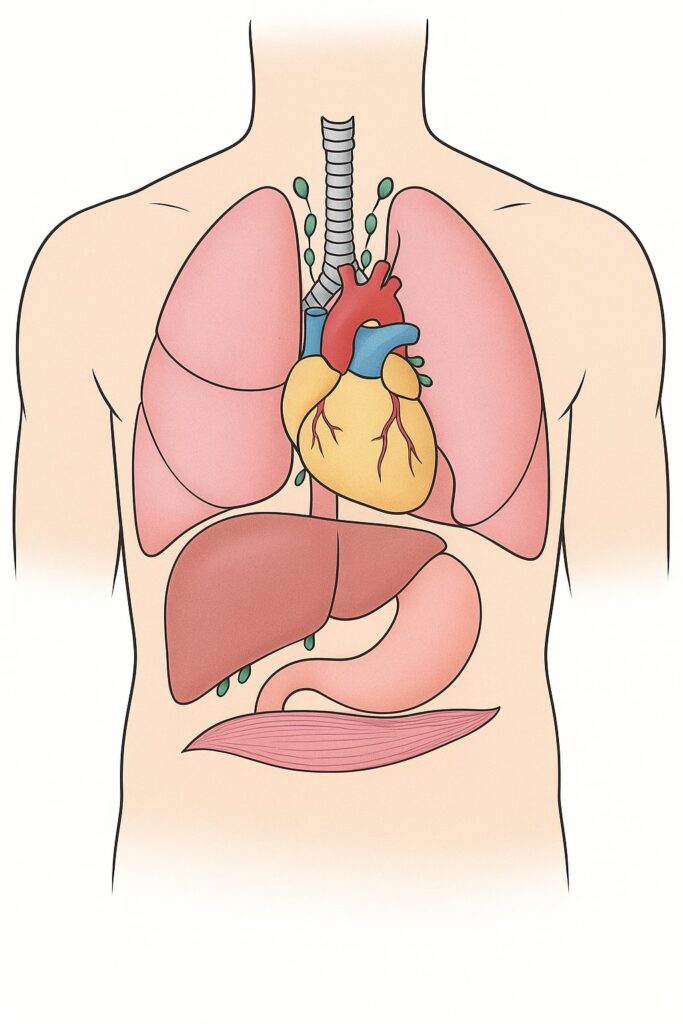

Zapalenie śródpiersia (mediastinitis) to stan zapalny przestrzeni w klatce piersiowej znajdującej się między płucami, mostkiem a kręgosłupem. Jest to poważne powikłanie, które w skrajnych przypadkach może prowadzić do śmierci.

Infekcja może przedostać się do śródpiersia różnymi drogami: bezpośrednio z ogniska zapalnego, a także przez krew lub limfę. Ropa jest tak agresywna, że potrafi niszczyć przegrody między mięśniami oraz ściany dużych tętnic. Dlatego stan zapalny szybko się rozprzestrzenia i może prowadzić do silnych krwotoków.

Najczęściej źródłem infekcji prowadzącej do zapalenia śródpiersia jest stan zapalny w okolicy wierzchołka korzenia zęba. Czasami współwystępuje on z infekcją migdałków lub uszkodzeniem błony śluzowej jamy ustnej.

Ostra lub przewlekła sepsa

Sepsa to najpoważniejsze powikłanie ropnia zęba. Rozwija się, gdy układ odpornościowy nie radzi sobie z infekcją, a ta rozprzestrzenia się po całym organizmie. W zależności od szybkości przebiegu wyróżnia się: sepsę piorunującą (1–2 dni), ostrą (5–7 dni), podostrą(1–2 tygodnie) oraz przewlekłą. W pierwszej kolejności uszkodzeniu ulegają płuca, a następnie inne narządy – wątroba, nerki itd. Stopniowo rozwija się wstrząs septyczny: krążenie w tkankach zostaje zaburzone, narządy przestają prawidłowo funkcjonować i pojawia się niewydolność wielonarządowa. W takim stanie większość pacjentów umiera w ciągu 2–3 dni.